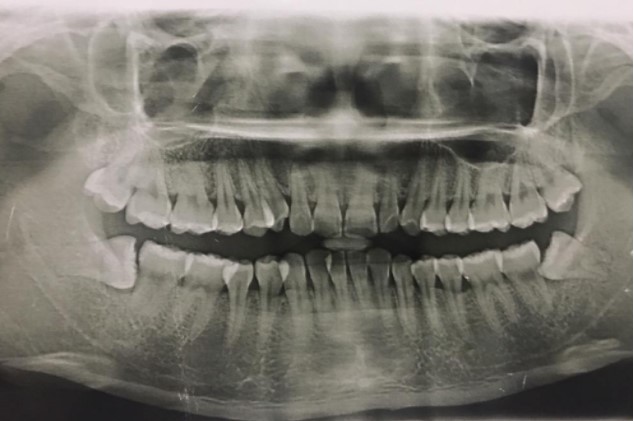

1、患者,男,38歲。上前牙變色1年,自述上前牙5年前受過外傷,唇側(cè)傾斜,檢查可見左上1牙冠變色,牙冠缺損近1/2,牙髓測(cè)試無反應(yīng),X線根尖片顯示患牙無明顯異常,全景片顯示雙側(cè)下頜智齒近中阻生,之前有發(fā)炎化膿病史,目前無咀嚼不適??谇黄溆酂o異常。

檢查情況及X線片見下圖:

(1)主訴診斷:左上1牙髓壞死(外傷)

(2)非主訴診斷:雙側(cè)下頜智齒冠周炎(近中阻生)